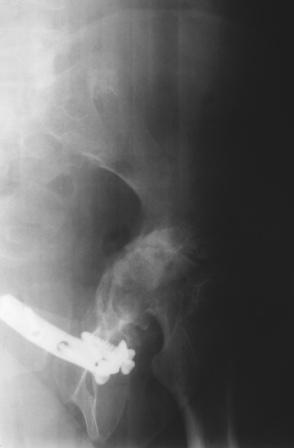

Уважаемые коллеги! Пациентка 32 года с застарелым повреждением таза, после остеосинеза лонного сочленения пластиной. Посоветуйте с выбором тактики и методик лечения.

Получила травму в феврале 2004г в г.Лобытнанги ЯНАО Тюм.обл. Через неделю после поступления выполнен остеосинтез лонного сочленения пластиной. 1,5 месяца на скелетном вытяжении. В последующем ходит при помощи костылей с нагрузкой на правую ногу. Имеется нестабильность половин таза, неправильно-консолидированный перелом левой вертлужной впадины, невропатия седалищного нерва слева. В результате невропатии седалищного нерва сформировалась эквинусная установка левой стопы,парестезии по подошвенной поверхности.

Клинически: ходит на костылях с нагрузкой на правую ногу. Левая стопа в эквинусе. Осевая нагрузка на левую н\конечность болезненна в области левого тазобедренного сустава, при прикосновениях к подошвенной поверхности стопы у пациентки чувство зжения. В левом коленном суставе полный обьем движений, в левом тазобедренном резко ограничено отведение и ротация, укорочение левой н\конечности на 2,5 см. При полипроекционной и функциональной Р-графии выявлена нестабильность левого КПС и лонного сочленения, консолидированный в порочном положении поперечный оскольчатый перелом левой вертлужной впадины с центральным смещением головки бедра. Нами выполнена коррекция деформации левой стопы. Планируется выполнить введение 2 канюлированных илиосакральных винтов слева, реостеосинтез лонного сочленения реконструктивной пластиной, после заживления ран - тотальное эндопротезирование левого тазобедренного сустава.